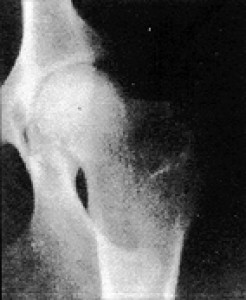

Snímky postižených kloubů: